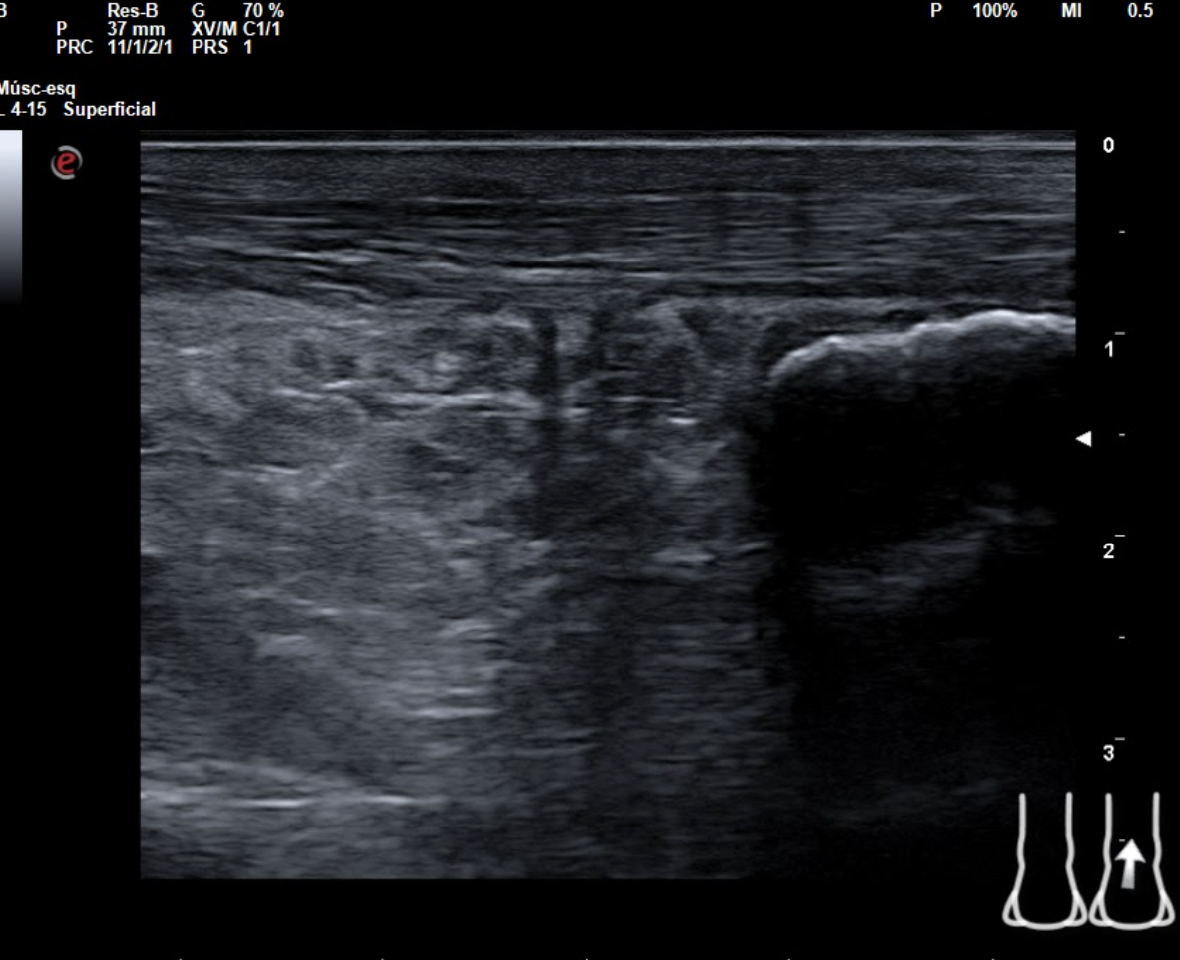

En tendón aquíleo izquierdo se aprecia rotura completa con solución de continuidad de 2 cm localizada a 5,7 cm de su inserción en el calcáneo. Presenta áreas hipoecoicas peritendón que sugieren hematoma secundario. En el aquíleo derecho presenta leve hipoecogenicidad y engrosamiento del tendón sin solución de continuidad que sugiere tendinosis. Importante componente inflamatorio. No datos de TVP. Poplítea y safena externa permeables y compresibles en ambas extremiedades.

Juicio clínico: Rotura completa de tendón de Aquiles izquierdo. Tendinosis aquílea derecha.